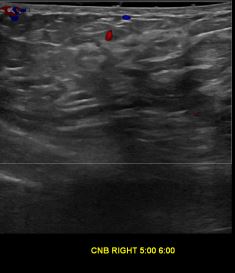

상기환자는 우측 유방 만져지는 멍우리로 내원하신 40대중반 여성분으로 의심스러운 우측혹 조직검사 시행해 제자리암으로 진단되었습니다